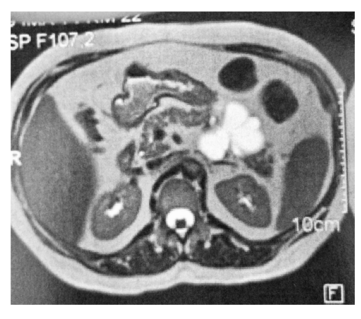

Um paciente, que apresentava pancreatite aguda necrótica complicada há seis semanas, foi submetido a um tratamento.

Com base nesse caso hipotético, é correto afirmar que o exame de controle imediato mostrado acima foi realizado após um tratamento